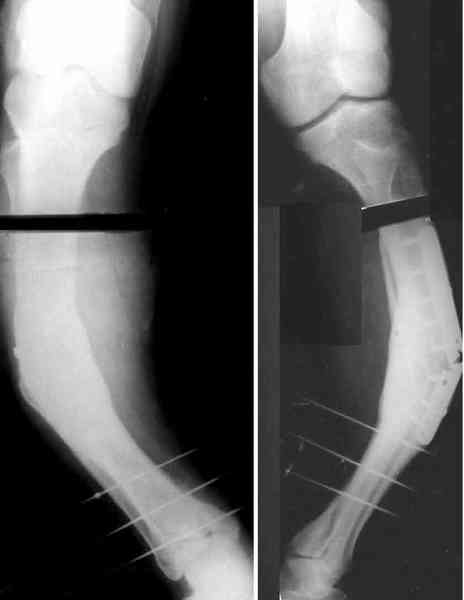

Для продолжения темы - несколько картинок.

Пациент 30 лет, лет пять назад оперирован по поводу перелома голени пластиной. Находясь на героине, нарушил режим, пошел, сломал и ногу и

пластину, но перелом сросся.

В приложении - внешний вид и рентген.

Мнения?

AC> Аппарат с шарнирами, чрескожная остеотомия, устранение угла.

Александр, как раз уровень остеотомии подробнее - на вершине деформации? Там Сломанная пластина.

Там не винты (может, плохо видно), а сломанная пластина, вросшая в кость.

a> Александр, как раз уровень остеотомии подробнее - на вершине

a> деформации? Там Сломанная пластина.

Ну, например, на уровне перелома пластинки. Можно пересечь часть кости, не прилежащую к пластинке, затем надломить остальное.

a> Там не винты (может, плохо видно), а сломанная пластина, вросшая в

a> кость.

Пластинку и винты мне удалось разглядеть только на профильной проекции, точнее, трехчетвертной, судя по виду коленного сустава (правый снимок). На фасной - вообще не могу разобрать, где она :( Но, в конце концов, можно и не видя ее сказать, что уровень остеотомии может быть и другим, ниже или выше пластинки, придется только компенсировать смещение по ширине, которое появится при полном устранении угла не на вершине.